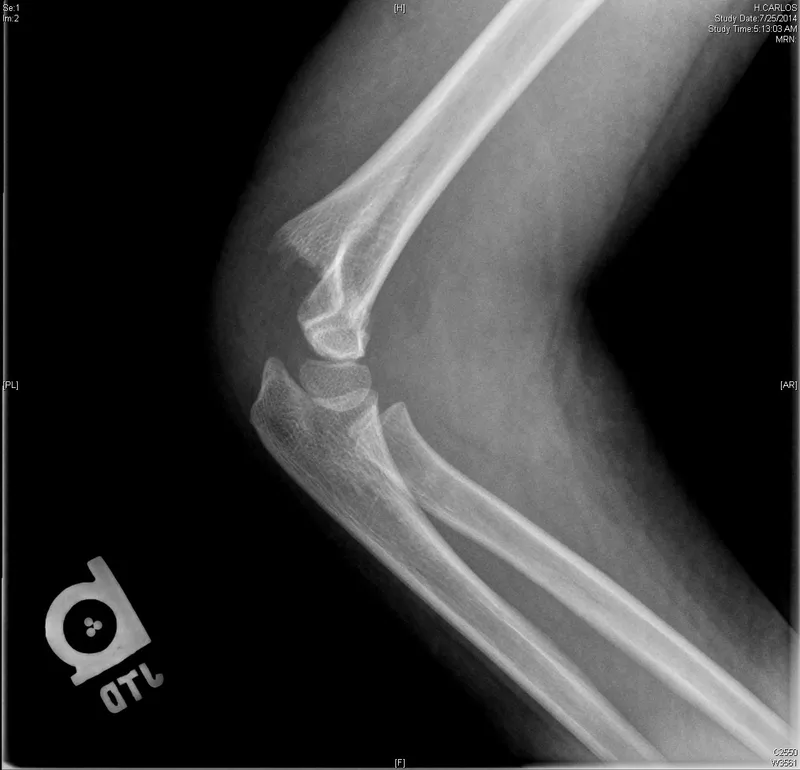

- Supracondylar Humerus: Most common elbow fracture (~60%). FOOSH mechanism. Gartland classification.

- Complications: Volkmann's ischemic contracture (brachial artery), nerve injury (Median > Radial > Ulnar). Anterior humeral line, Baumann's angle assessment.

- Tx: Type I: Cast (~3 wks); Type II/III: Closed reduction & percutaneous pinning (CRPP).

⭐ In supracondylar humerus fractures, posteromedial displacement is commonly associated with radial nerve injury, whereas posterolateral displacement often compromises the median nerve and brachial artery.